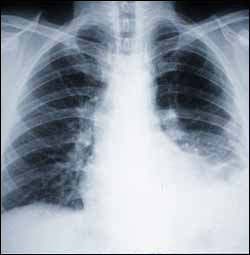

Asbestos is toxic. The inhalation of asbestos fibers can cause serious illnesses, including malignant mesothelioma, lung cancer, and asbestosis (also called pneumoconiosis). Since the mid 1980s, many uses of asbestos have been banned in several countries.

Signs and symptoms of mesothelioma include shortness of breath due to pleural effusion (fluid between the lung and the chest wall), chest wall pain, and constitutional signs such as unexplained weight loss. The diagnosis may be suspected based on chest X-ray and CT scan findings, but must be confirmed either by examining serous effusion cytology or with a biopsy (removing a sample of the suspicious tissue). A thoracoscopy (inserting a tube with a camera into the chest) can be used to acquire biopsy material, and allows the introduction of substances such as talc to obliterate the pleural space (a procedure called pleurodesis), preventing more fluid from accumulating and pressing on the lung. Despite treatment with chemotherapy, radiation therapy or sometimes surgery, mesothelioma carries a poor prognosis. Research about screening tests for the early detection of mesothelioma is ongoing.